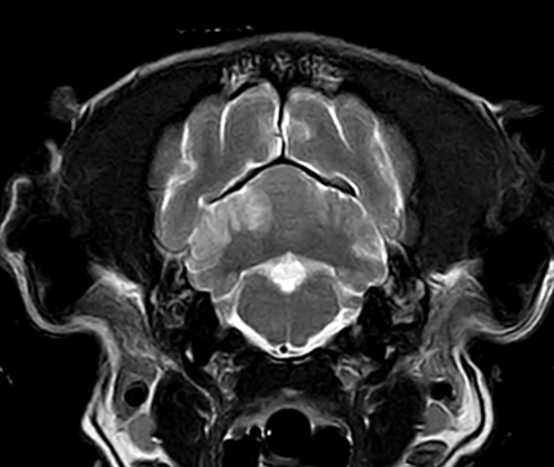

3T MRI

기존 본원에서 이용하던 1.5T 장비와 비교하여 높은 해상도와 빠른 스캔 시간(촬영 부위 당 30분 미만)으로 MR 촬영 시 환자의 마취 부담을 줄일 수 있습니다.

3T MRI는 국내 동물병원에서 최상급 촬영 장비에 해당하며 본동물의료센터의 MRI는 3T MRI 중에서도 하이엔드급 장비(Philips Ingenia)를 사용하고 있습니다.

두개 내 출혈(개)

소뇌 경색(개)

뇌 수두증(고양이)

01뇌 MRI

· 뇌신경계 질환의 정확한 감별 및 조기진단

· 뇌수두증, 뇌출혈, 뇌종양, 뇌수막염, 소뇌탈출 등

· 전정계(중이, 내이) 질환의 진단

· 안구질환의 진단